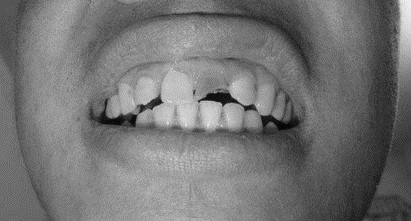

1、患者,男,38歲。上前牙變色1年,自述上前牙5年前受過外傷,唇側(cè)傾斜,檢查可見左上1牙冠變色,牙冠缺損近1/2,牙髓測(cè)試無(wú)反應(yīng),X線根尖片顯示患牙無(wú)明顯異常,全景片顯示雙側(cè)下頜智齒近中阻生,之前有發(fā)炎化膿病史,目前無(wú)咀嚼不適??谇黄溆酂o(wú)異常。

檢查情況及X線片見下圖: